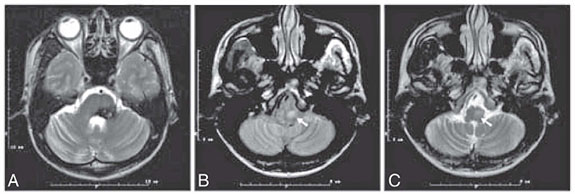

Fig4 (below) MR images obtained in a patient

with brainstem cavernous angioma. (A) Axial T2-weighted image shows

hyposignal suggesting hemosiderin deposits in the left tegmentum of the

pons. (B,C) axial PD/T2- weighted images show hypersignal at the

level of the left medullary olive which appears also enlarged in

comparison to the right one. The signal change is more apparent on the

PD-weighted image (B). |